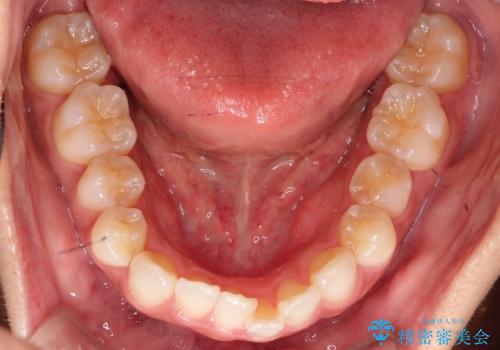

前歯の叢生を非抜歯で改善|インビザライン+IPR・遠心移動・FIX保定

- 前歯部のガタガタ(叢生)を非抜歯で改善するため、インビザラインによるマウスピース矯正を計画しました。抜歯は行わず、歯間をわずかに削るIPR(ディスキング)と奥歯を後方に移動させる遠心移動を併用して、歯を並べるスペースを確保します。歯列が整った後は、FIXリテーナー(固定式保定装置)で後戻りを防止し、安定した歯並びを維持します。

歯を抜きたくないというご希望に応え、インビザラインを用いて非抜歯で歯列を整えました。前歯に必要なスペースを確保するため、歯間をわずかに削るIPRと奥歯を後方に移動する遠心移動を組み合わせました。これにより自然で美しい歯並びを実現。治療終了後は、歯の裏側に目立たないFIXリテーナーを装着し、歯列の後戻りを効果的に防ぎました。患者様は治療中も審美的にストレスなく過ごされ、満足度の高い結果を得られました。